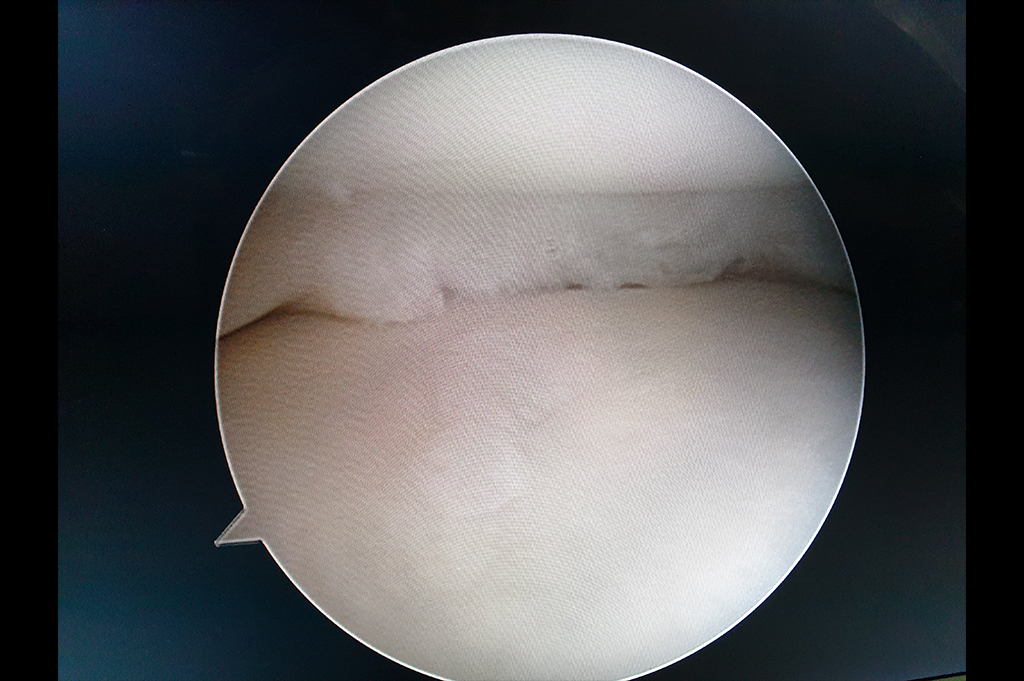

Arthroscopy - ACL Reconstruction, Maniscus Injury